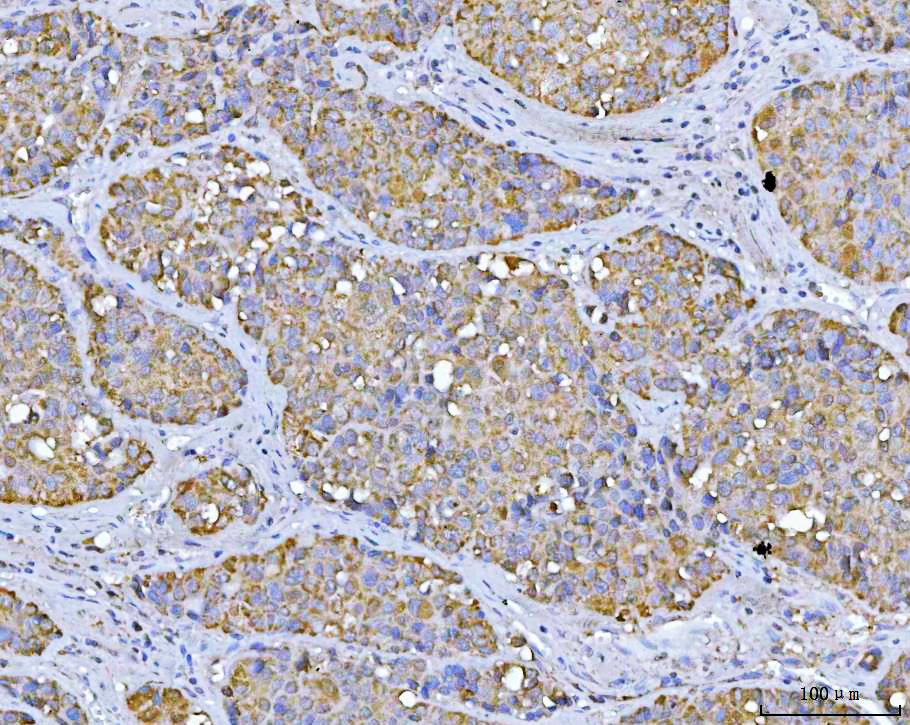

IHC analysis of VDAC1 using anti-VDAC1 antibody (BA3754).

VDAC1 was detected in a paraffin-embedded section of human liver cancer tissue. The tissue section was developed using HRP Conjugated Rabbit IgG Super Vision Assay Kit (Catalog # SV0002) with DAB (Catalog # AR1027) as the chromogen.